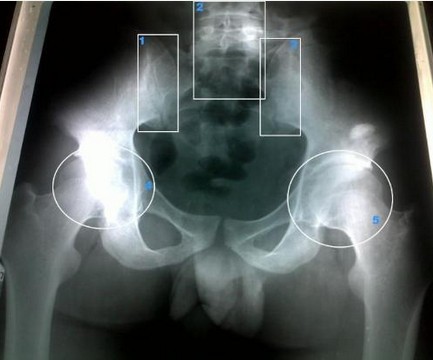

大家都清楚的一件事就是强直患者会出现背部疼痛的情况的,所以很多的时候都会有误诊的情况,因为有些患者根本不是强直疾病,只是一些简单的机械性的疼痛,但是通过计算机断层扫描之后,就会发现具有明显的骶髂关节炎特征,这是作为强直的重要判断之一的!

【3】CT检查

有很多患者在做了X线检查之后仍然会对自己的病情没有办法去确定,此时患者就可以进行CT检查!